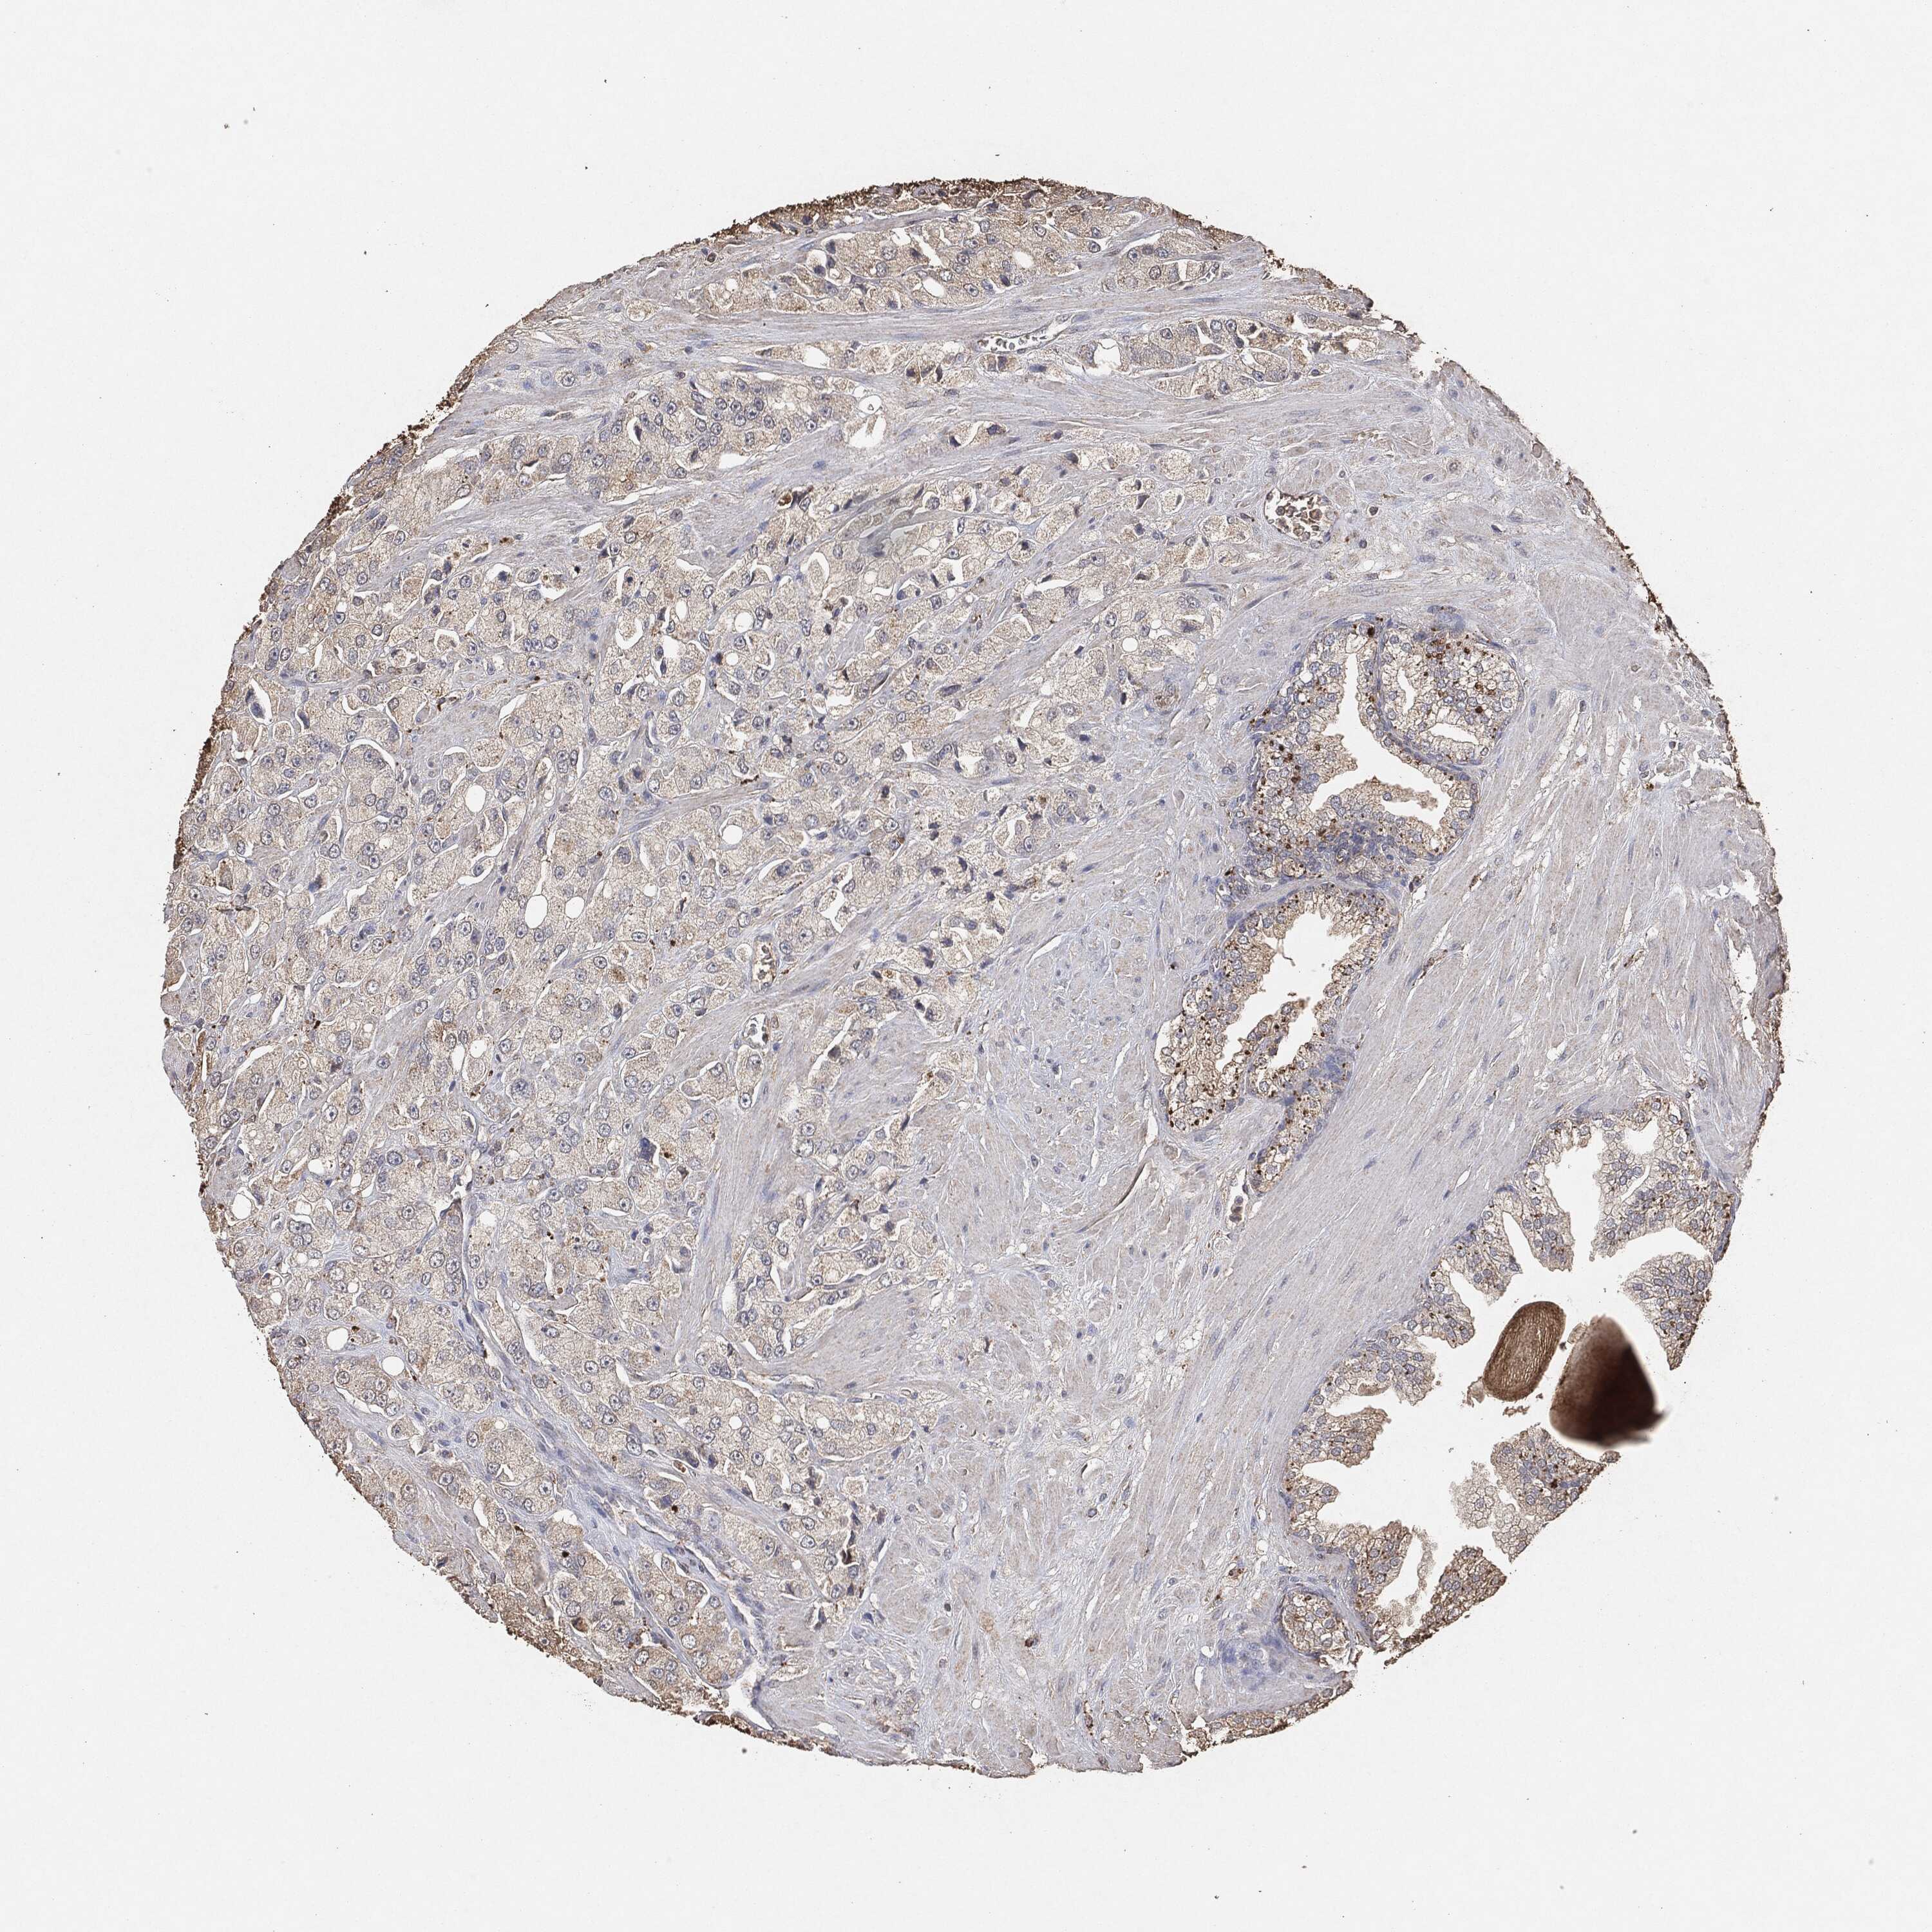

PROSTATE CANCER - Protein expressioni

A mouse-over function shows sample information and annotation data. Click on an image to view it in a full screen mode. Samples can be filtered based on level of antibody staining by selecting one or several of the following categories: high, medium, low and not detected. The assay and annotation is described here.

Note that samples used for immunohistochemistry by the Human Protein Atlas do not correspond to samples in the TCGA dataset.

Antibody stainingi

Antibody staining in the annotated cell types in the current human tissue is reported as not detected, low, medium, or high, based on conventional immunohistochemistry profiling in selected tissues. This score is based on the combination of the staining intensity and fraction of stained cells.

Each image is clickable and will lead to virtual microscopy that enables deeper exploration of all samples and also displays staining intensity scores, fraction scores and subcellular localization as well as patient and tissue information for each sample.

Adenocarcinoma, Medium grade

Adenocarcinoma, Low grade

Adenocarcinoma, High grade

Adenocarcinoma, NOS